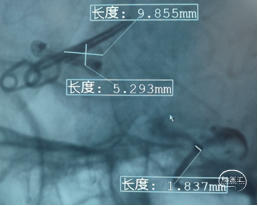

直接测量:7.4x3.92mm

3D测量:7.22x5.35mm

对比测量:8.9x4.8mm(偏大10%)